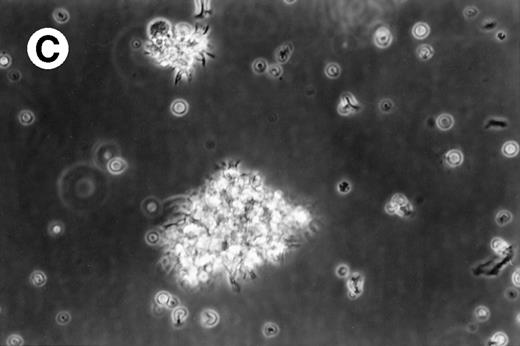

Cultures of AML cells were replenished with fresh medium and cytokines every 3 to 4 days. Cells cultured in various cytokine combinations were assessed for total number of viable cells and cells with dendritic morphology after various culture periods. Approximately 25% to 45% of the initial cell population was recovered after 9 days of culture. No significant change in numbers of cells was observed between day 9 and day 20 of culture (not shown). Similar yields of viable cells were noted for AML cell cultures from other patients. Freshly isolated AML PBMNC displayed a spherical morphology without discernable cells exhibiting dendritic processes (Fig 1A). Between days 10 and 14, cultures with GM-CSF, IL-4, and TNF-α (Fig1B) or GM-CSF, IL-4, and CD40L (Fig 1C) consistently displayed an increase in cell size and showed cell clusters with dendritic morphology in all but one AML patient (patient 16).

Morphology of freshly isolated and cultured AML cells. Phase contrast micrographs of freshly isolated AML PBMNC (A; 100× origonal magnification); AML cells cultured for 14 days in GM-CSF, IL-4, and TNF (B; 250× original magnification); or GM-CSF, IL-4, and CD40L (C; 250× origianl magnification). (A and B) Obtained with cells from patient 13; (C) Obtained with cells from patient 18.